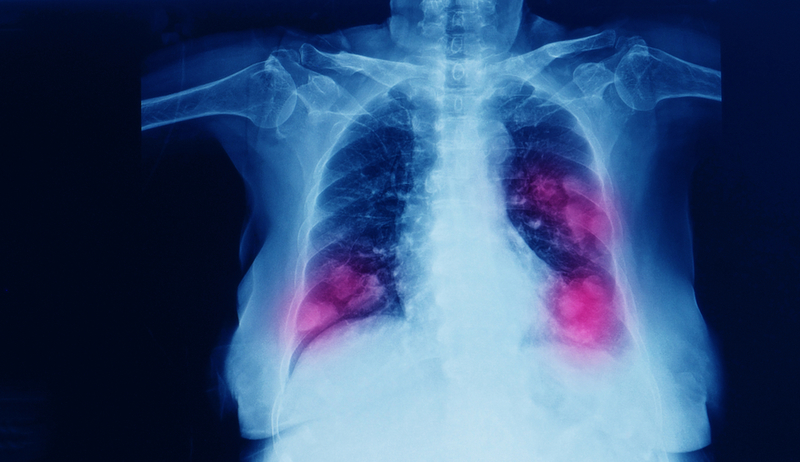

Researchers have found that that nicotine, a non-carcinogenic chemical found in tobacco, actually promotes the spread of lung cancer cells into the brain where they can form deadly metastatic tumours.

Smokers are far more likely to develop lung cancer than non-smokers, the study said. "Based on our findings, we don't think that nicotine replacement products are the safest way for people with lung cancer to stop smoking," said study lead author Kounosuke Watabe from Wake Forest School of Medicine in the US. Around 40 percent of lung cancer patients also develop brain metastasis, but new research has found this number is dramatically higher among smokers.

In the study, published in the Journal of Experimental Medicine, the research team first examined 281 lung cancer patients and found that cigarette smokers exhibited a significantly higher incidence of brain cancer. Then, using a mouse model, the researchers discovered that nicotine enhanced brain metastasis by crossing the blood-brain barrier to change the microglia - a type of immune cell in the brain - from being protective to supporting tumour growth. The team then looked for drugs that might reverse the effects of nicotine and identified parthenolide, a naturally occurring substance in the medicinal herb feverfew, which blocked nicotine-induced brain metastasis in the mice. Because feverfew has been used for years and is considered safe, the researchers believe parthenolide may provide a new approach to fight brain metastasis, particularly for patients who have smoked or still smoke.